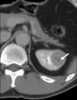

Segmental cystic disease

Caroli disease (communicating cavernous ectasia, or congenital cystic dilatation of the intrahepatic biliary tree) is a rare inherited disorder characterized by cystic dilatation (or ectasia) of the bile ducts within the liver. There are two patterns of Caroli disease: focal or simple Caroli disease consists of abnormally widened bile ducts affecting an isolated portion of liver. [Source: Wikipedia ]